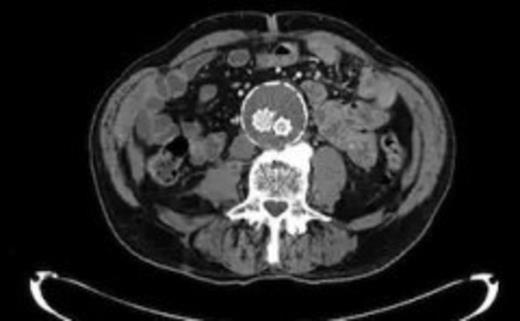

The patient's condition improved quite rapidly and the intravenous antibiotics were stopped and replaced with oral ciprofloxacin upon microbiological advice (for a total of six weeks). The drain was removed after 2 weeks when the series of repeat CT scans showed the abscess had nearly completely resolved (Fig. 5). Further CTs on follow up at 6 weeks and 3 months post discharge show no collection at all. At the last clinic visit 6 months following his last admission the patient was enjoying good health.

Near complete resolution of psoas collection after 2 weeks of intravenous antibiotics